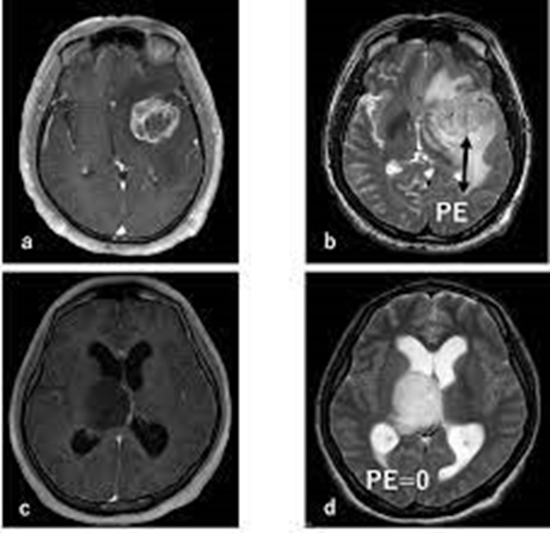

بررسی ارزش تشخیصی DWIو ADC و perfusion MRI و MRS در افتراق ادم ریکتیو از ادم اینفیلتراتیو در بیماران مبتلا به گلیومای مغزی

ارزش تشخیصی DWIو ADC و perfusion MRI و MRS در افتراق ادم ریکتیو از ادم اینفیلتراتیو در بیماران مبتلا به گلیومای مغزی